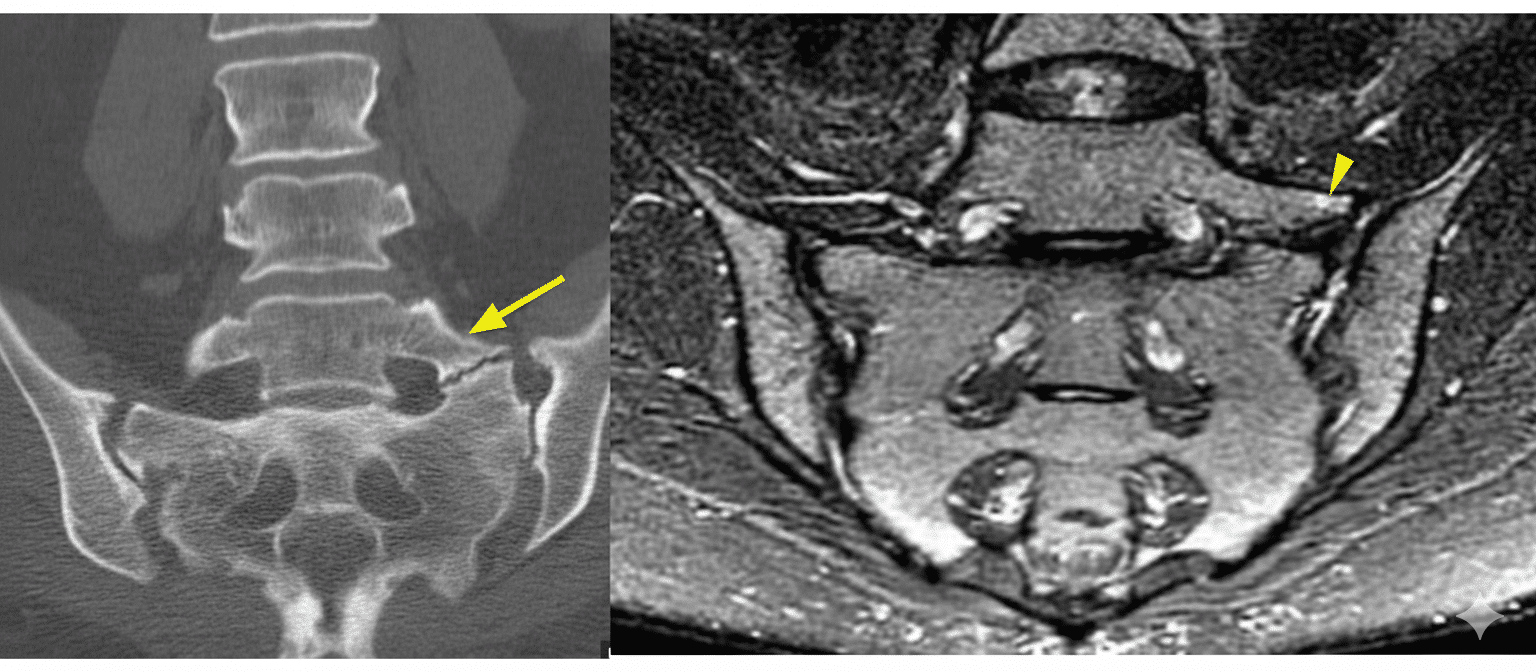

o TC → precisa la anatomía ósea y los osteofitos.

o RM → evalúa discos, raíces y edema en la pseudoarticulación.